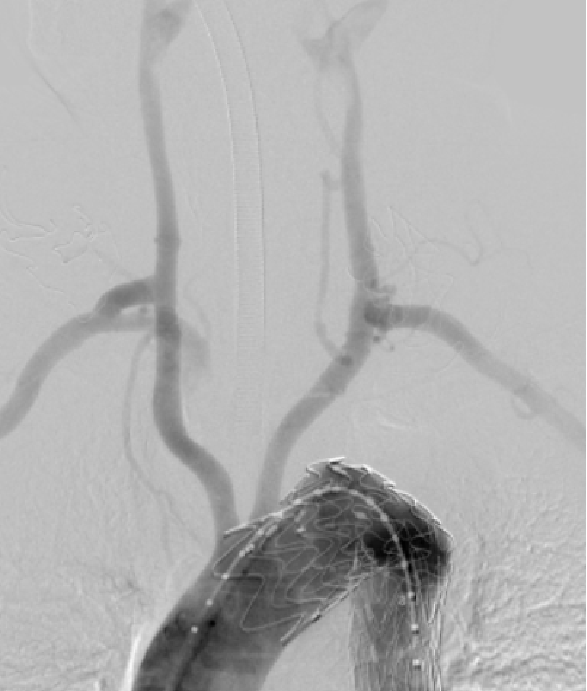

★原位开窗技术

关键在于穿刺器具和脑保护流程。

多中心研究(n=513):技术成功率98.6%,30天死亡率2.5%,内漏率1.6%,长期再干预率3.6%。球囊辅助破膜系统大大提高了手术精确性。